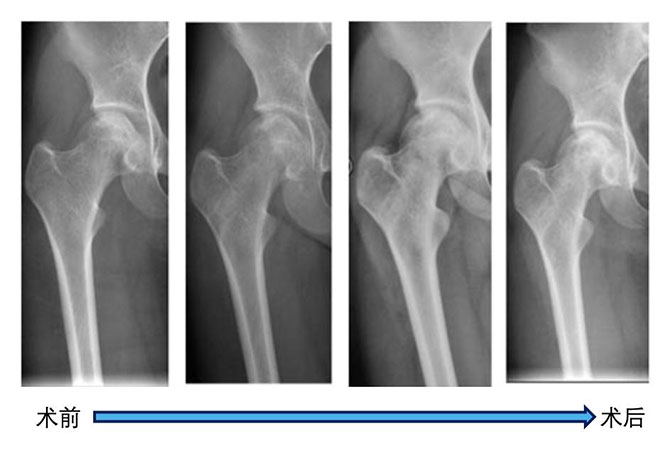

关节骨病与创伤科郑秋坚教授团队自2009年起开始对股骨头坏死的保髋治疗进行了大量研究,先后提出髓芯减压联合打压植骨,髓芯减压、打压植骨结合骨髓浓集物、髓芯减压、打压植骨、骨髓浓集物结合生物陶瓷棒的治疗方法,取得了满意的疗效,研究成果多次发表在国际干细胞转化应用研究的专业杂志《Stem Cell Research & Therapy》。

该方法采用微创技术,通过患者大腿外侧的一个1.5厘米长的切口,先将股骨头里面的坏死骨清除,把事先制备好的骨髓浓集物包被在作为载体的自体骨或生物陶瓷上,植入骨坏死区,直达股骨头软骨下,让这些骨髓中富含的间充质干细胞和生长因子在骨内微环境调节下分化为成骨细胞,起到修复骨坏死、重建股骨头结构的作用。